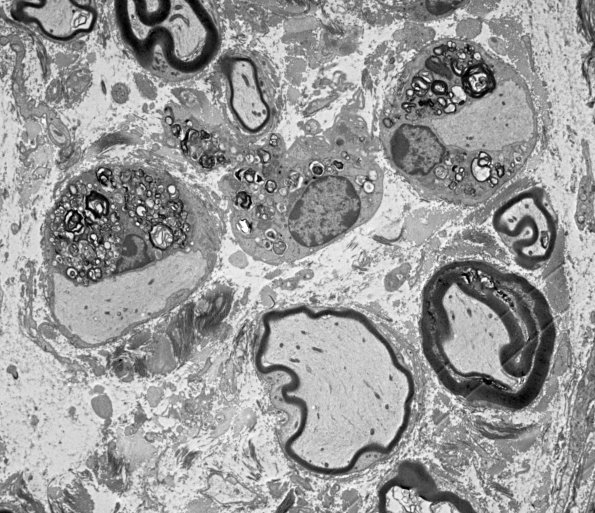

Washington University Experience | PERIPHERAL NEUROPATHY | 6 AXONAL DEMYELINATION (BASIC PROCESS) | 2A2 Mouse #33089 (Case 2) 064.jpg

Higher magnification of image #2A1. (electron micrograph)